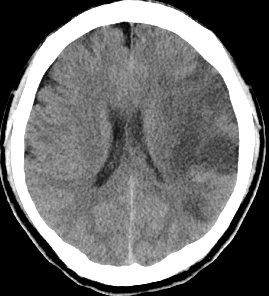

くも膜下出血のCT

【くも膜下出血のCT】